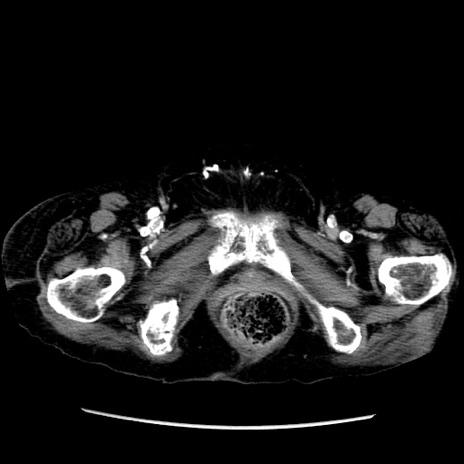

症例14(横断像)

【症例】 90歳代女性

【主訴】 腹痛・嘔吐

【現病歴】今朝から左側腹部痛を認めた。 経過観察していたが、嘔吐を認めたため来院。

【既往歴】 子宮癌術後

【身体所見】 意識清明、BP 127/54mmHg、P 98bpm Sp02 95%(RA)、BT 35.8°C、腹部平坦・軟腸ぜん動音聴取良好、右下腹部圧痛(+) 反跳痛なし

【データ】WBC 9800、CRP 0.46